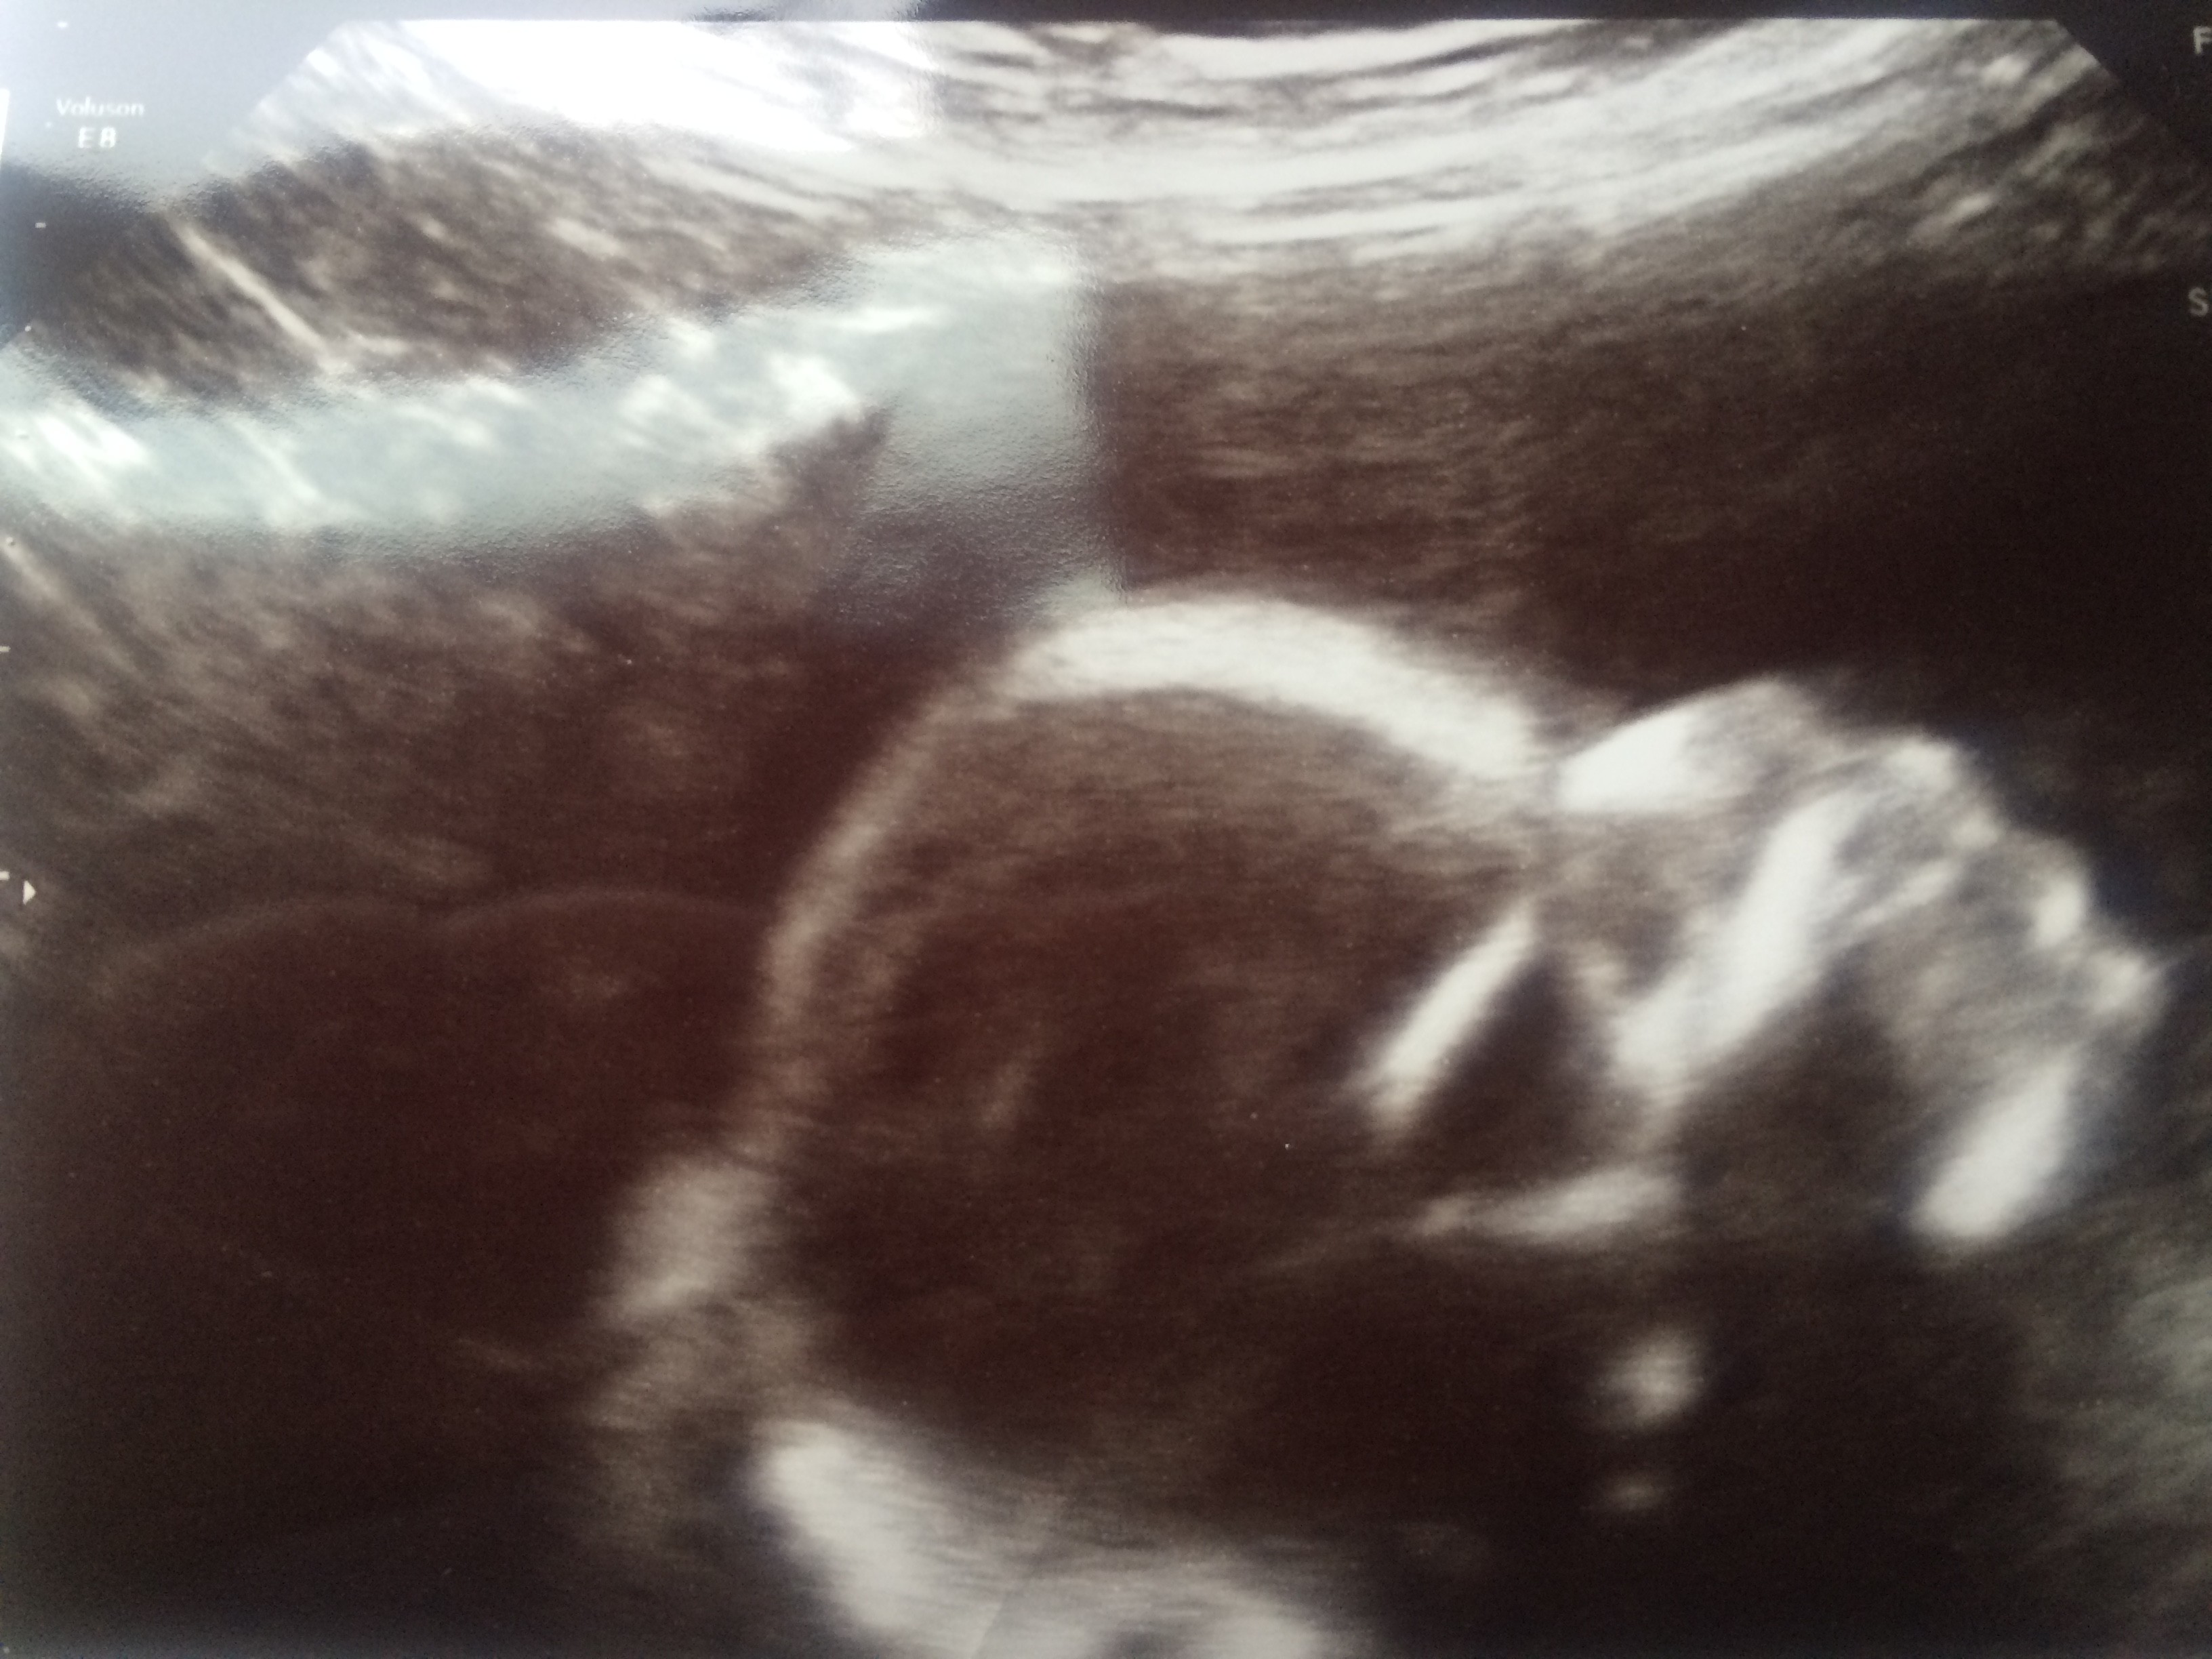

We had our anatomy scan a couple weeks ago. And the first thing we saw was our baby’s spine. And it was glorious. I tell you I’ve never seen such a beautiful spine. And arms and legs and fingers and toes and a clearly beating heart to go with. It was a totally different experience than the first ultrasound. That one felt abstract, removed. I didn’t quite believe that it was real, that it wasn’t some kind of piped in feed. This one…I felt like I was looking at our baby. And every time the little thing kicks (or punches or any number of other sensations), I am delighted.